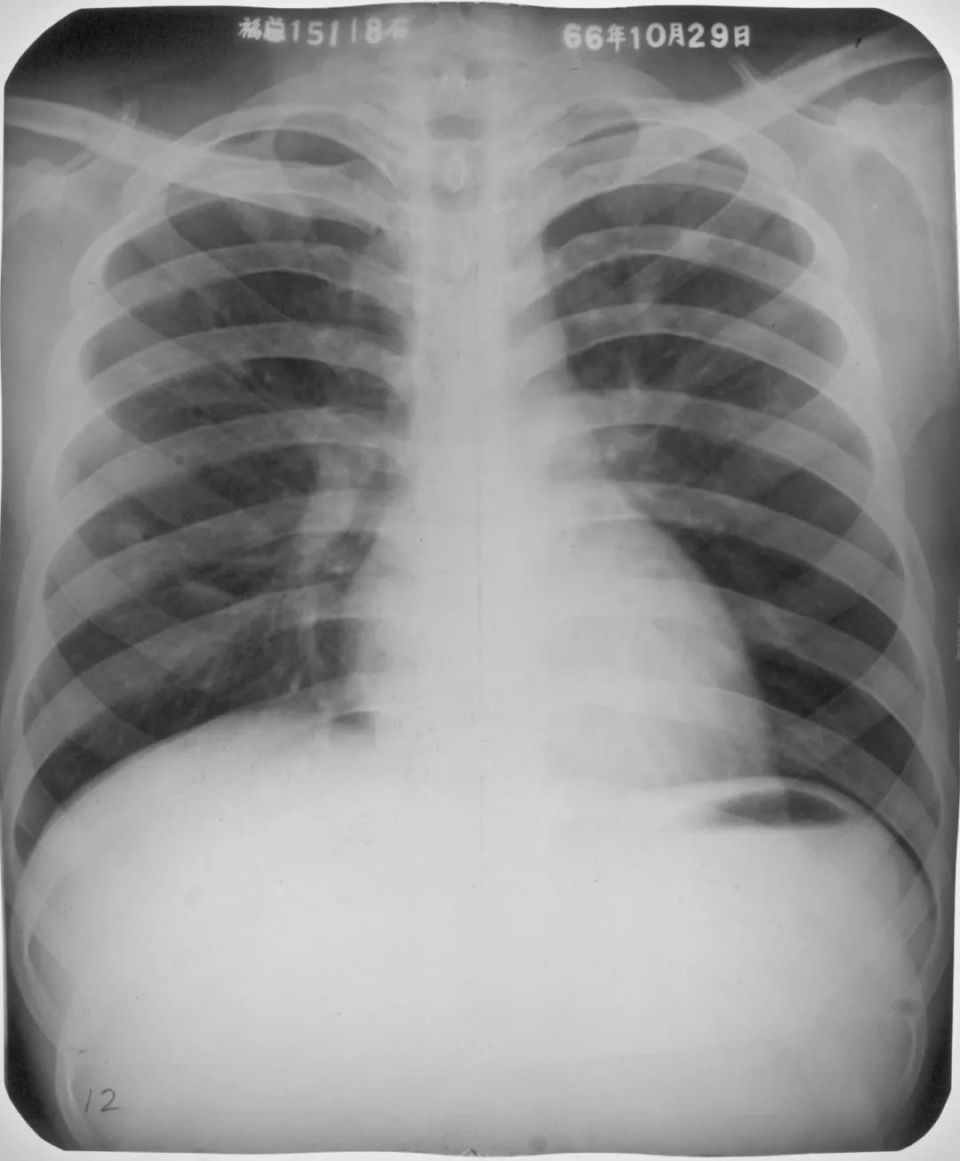

右肺中叶支原体肺炎

图片

胸部正位片示:右肺中叶肺纹理增粗,见斑片状阴影,密度不均匀,局部呈扇形自肺门部发出(箭头所指)